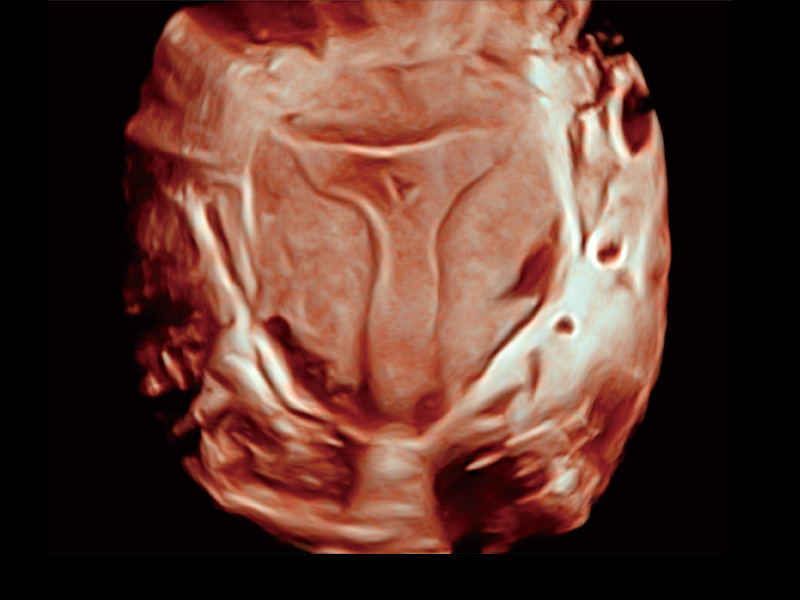

中央型宫腔粘连

腔内三维成像技术获得显著提升,超大扇角在满足日常基础扫查的同时,支持卵泡自动测量及多种三维渲染模式,为您提供更多的诊断信息,尤其是在子宫畸形的诊断,内膜及肿瘤占位观测中起到了重要的作用。